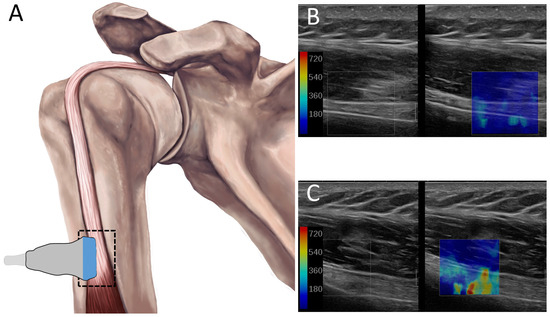

In Vivo Long Head of the Biceps Tendon Stiffness Varies with Forearm Position During Active Contraction: Implications for Personalized Rehabilitation After SLAP Lesions

Background/Objectives: Type II superior labrum anterior–posterior (SLAP) lesions of the long head of the biceps (LHB) tendon are associated with excessive tendon loading and are commonly treated surgically using SLAP repair, tenotomy, or tenodesis. These procedures alter musculotendinous length and loading and may affect functional outcomes, including forearm supination strength. Appropriate restoration of tendon tension is critical for favorable muscle adaptation and recovery. Shear wave elastography (SWE) is a non-invasive imaging technique capable of quantifying tissue stiffness as a surrogate for in vivo musculotendinous tension. This study aimed to characterize LHB tendon tension across forearm positions and loading conditions to improve the understanding of functional tendon loading relevant to postoperative activation and rehabilitation. Methods: In this controlled laboratory study, thirteen healthy female volunteers without shoulder pathology were assessed using SWE with the elbow positioned at 90° flexion. LHB tendon tension was measured in forearm pronation and supination under passive, active (unresisted), and weighted conditions. Paired t-tests were used to compare forearm positions within each loading condition. Results: LHB tendon tension was significantly greater during active and weighted conditions compared with passive loading in the pronated position (p < 0.05). During active contraction, tendon tension was significantly lower in supination than pronation (p < 0.05), whereas no positional differences were observed under passive or weighted conditions. Relative to passive loading, tendon tension increased by approximately 18.2% and 89.2% in supination, and 67.0% and 97.9% in pronation during active and weighted conditions, respectively. Conclusions: Forearm position selectively influences LHB tendon tension during active, unresisted contraction. Forearm orientation affected LHB tendon stiffness primarily during active, unweighted contraction, where pronation resulted in higher stiffness than supination. On the other hand, stiffness outcomes measured during passive and weighted positions were comparable between forearm orientations, indicating that positional effects are most evident when tendon loading is primarily muscle-driven. These findings highlight the relevance of forearm positioning during early postoperative activation and provide normative in vivo reference data to inform personalized rehabilitation strategies and future investigations of postoperative tendon loading following SLAP lesion treatment.